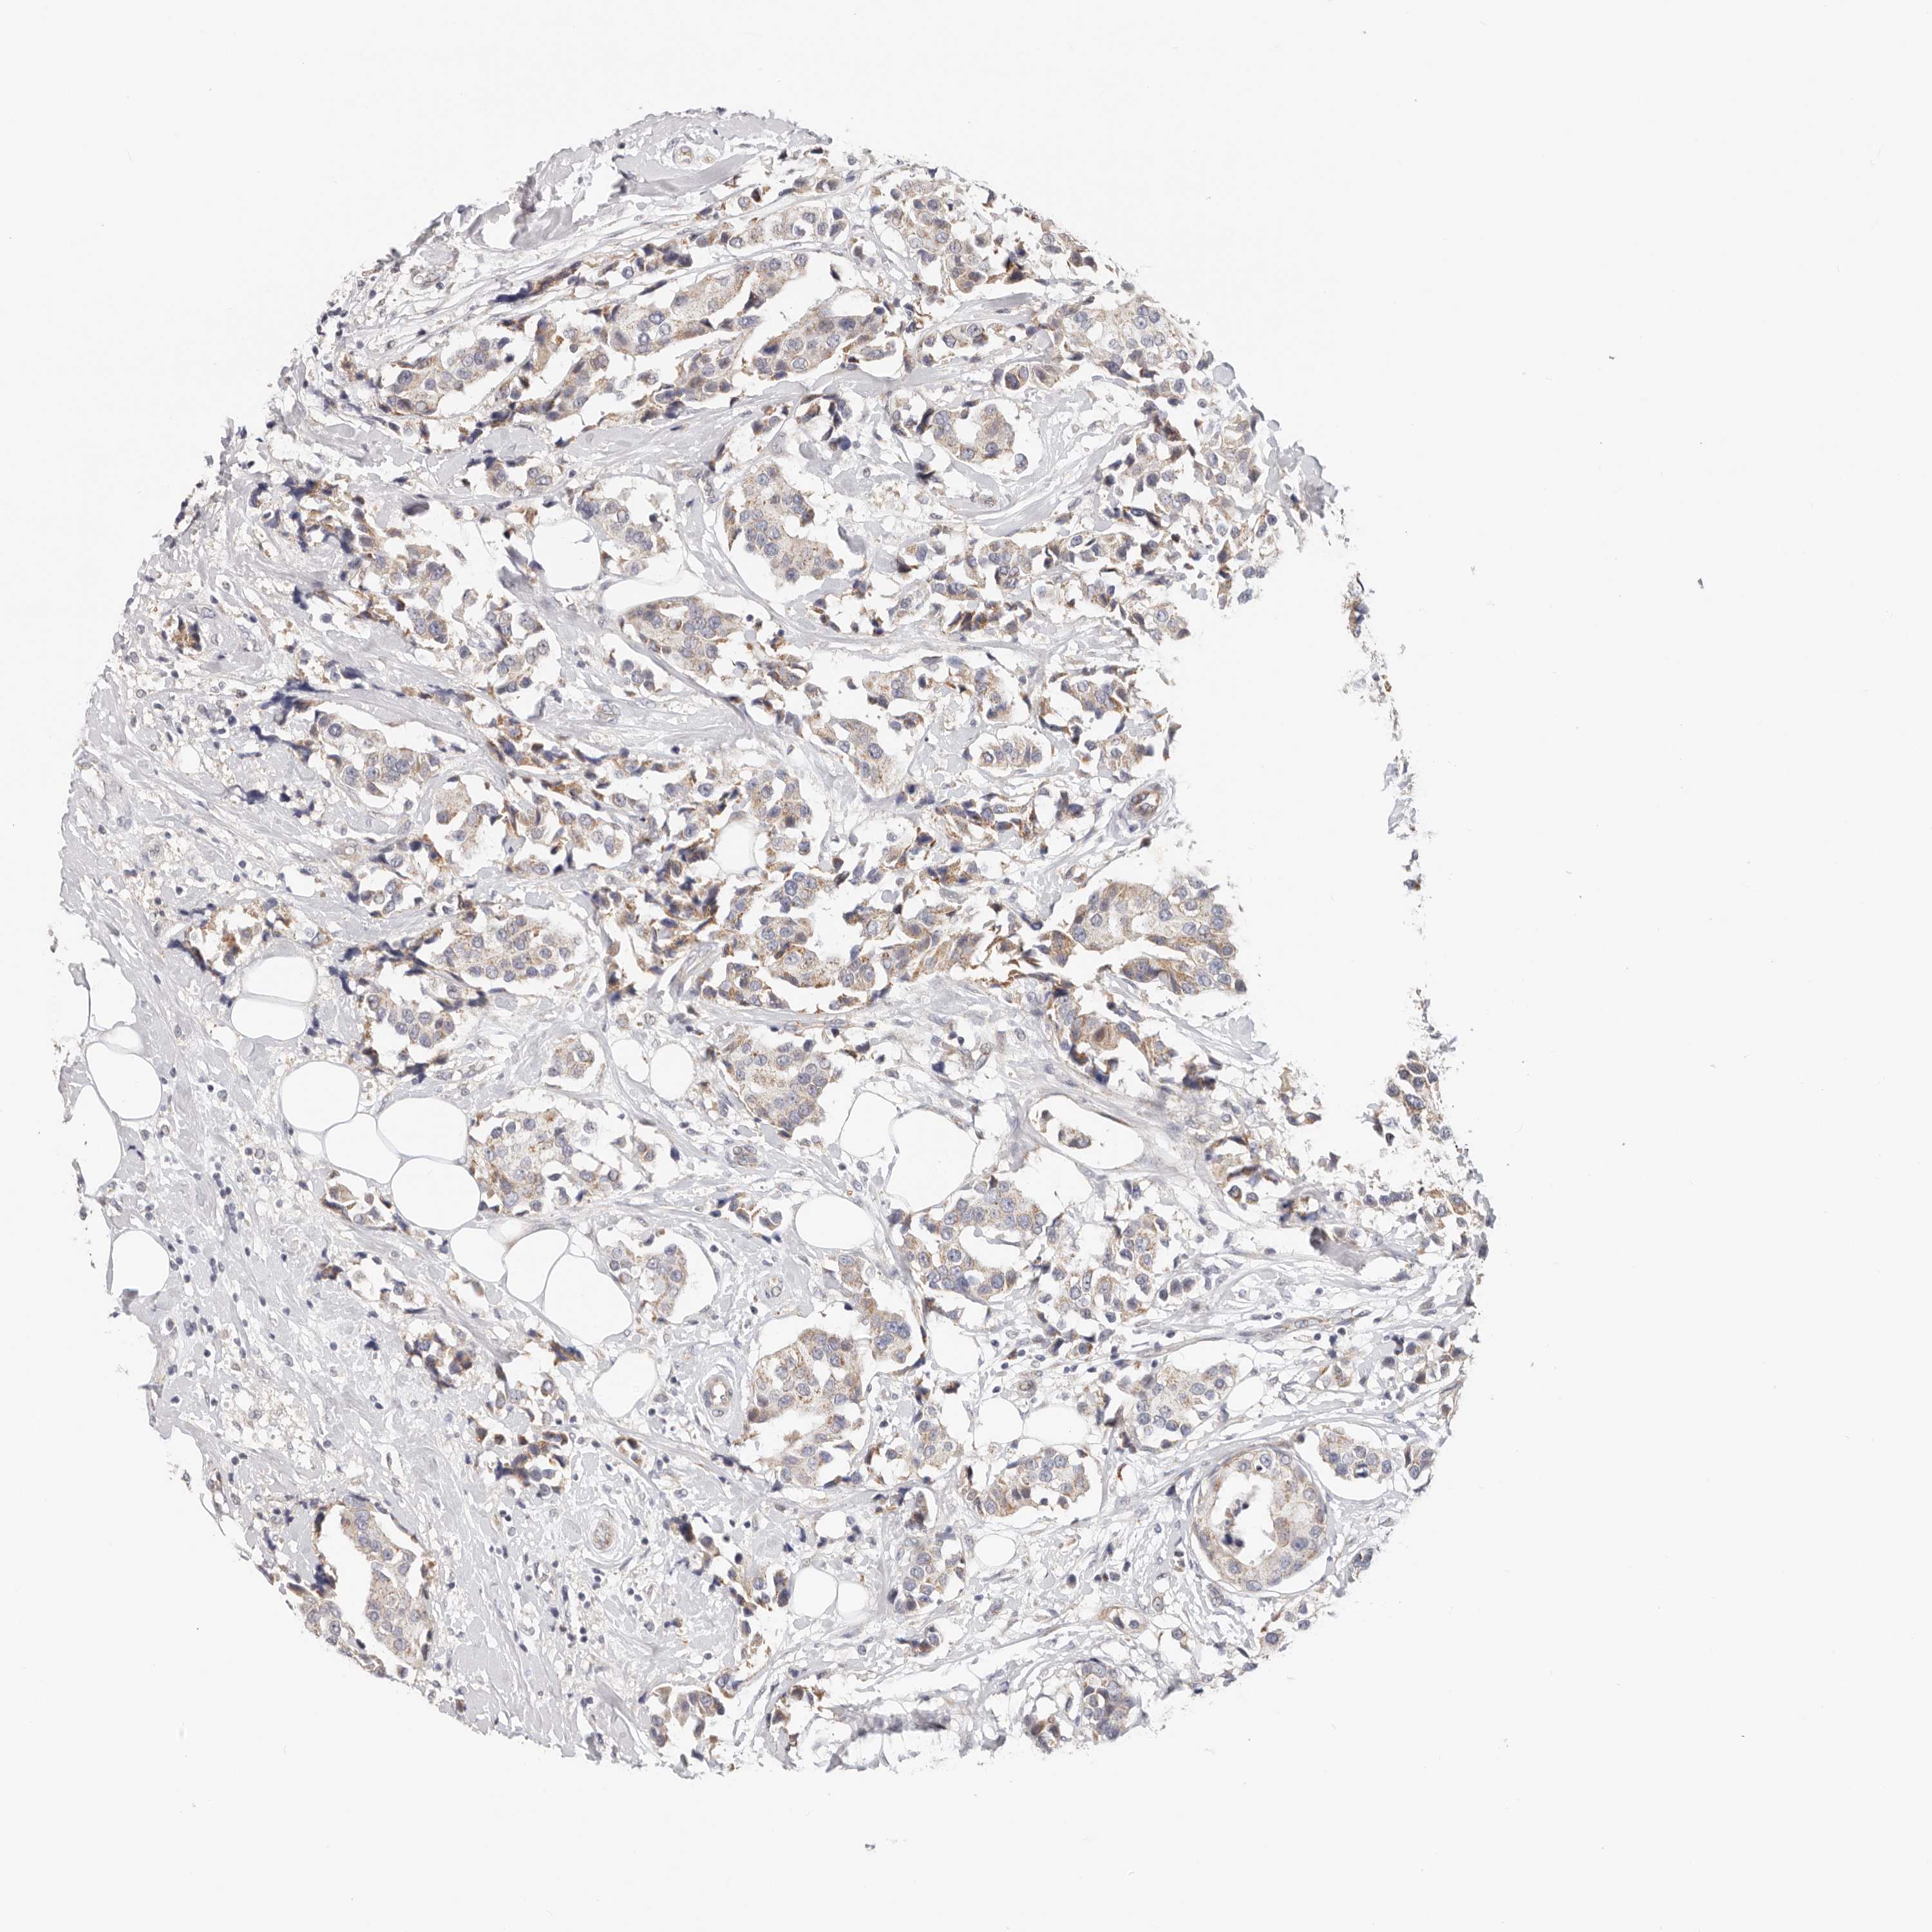

CANCER BREAST CANCER Show tissue menu

BRCA TCGA BRCA VALIDATION PROTEIN EXPRESSION

Breast cancer

Human cancer